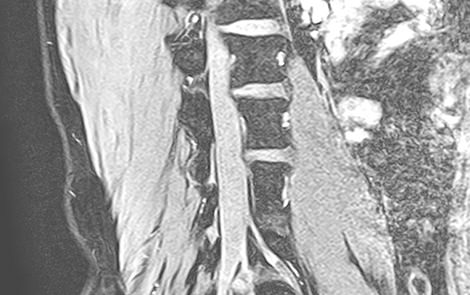

MRI

MRIとは磁気共鳴画像撮影法のことで正式には「Magnetic(磁気) Resonance(共鳴) Imaging(画像)」といいます。

1.5テスラMRI装置Vantage Elan(キャノンメディカルシステムズ製)を導入しておりレントゲン検査では評価しづらい骨の内部や軟部領域の精査が可能で、脊椎・四肢など整形外科領域の幅広い部位の検査を行っています。撮影部位にもよりますが検査には約20~40分ほど時間がかかります。低侵襲で安全な検査ですが強い磁気を使うので金属類は外して検査を行います。通常予約待ちの多いMRI検査ですが当院では医師の指示のもと初診時の当日検査も可能でスムーズかつ的確な診断、検査待ちの解消にも努めています。